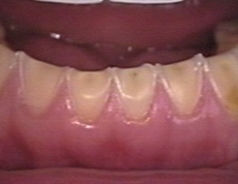

Kenmerken van tanderosie

In het beginstadium merkt u weinig van tanderosie. Pas in een later stadium kan tanderosie gevoeligheid bij eten en drinken veroorzaken. Het glazuur van uw tanden en kiezen wordt dunner. Dit veroorzaakt de gevoeligheid. Maar ook het uiterlijk van uw gebit verandert. De tanden worden geler, doordat het donkerder gekleurde dentine meer zichtbaar wordt. De tanden en kiezen kunnen ook kleiner worden.